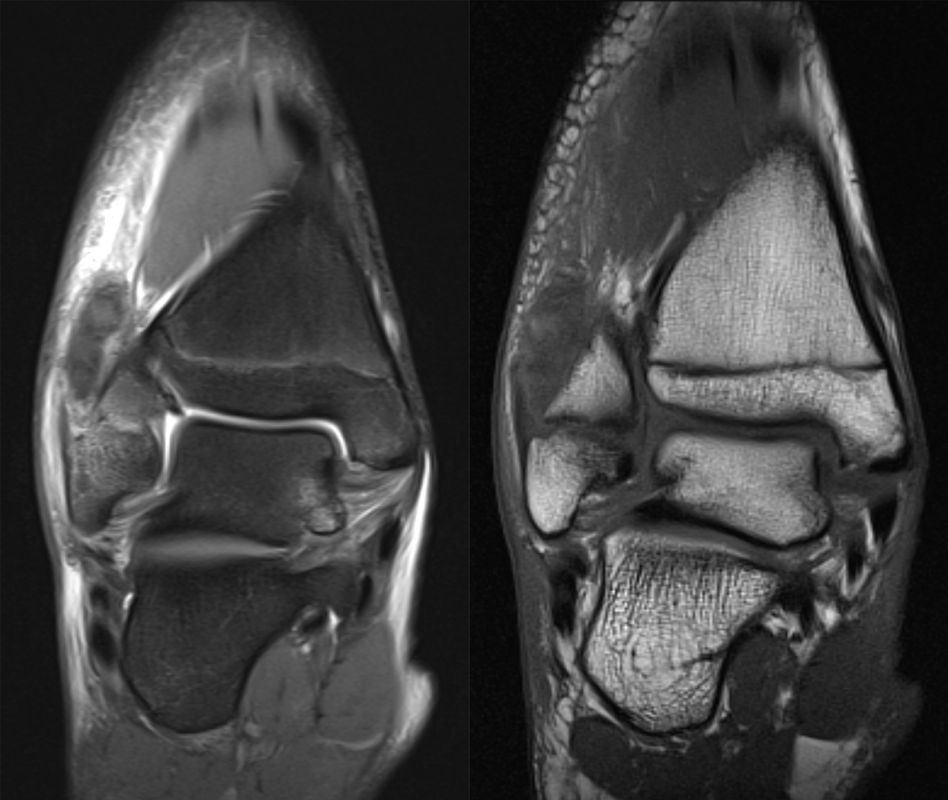

MRT

Die Kernspintomographie hat ihre Stärke in der Darstellung von Weichteilverletzungen. Insbesondere Verletzungen der Wachstumsfuge, des Periosts und der Bänder lassen sich gut visualisieren. Nachteilig ist die Untersuchungsdauer von 20-30 Minuten. Bleibt das Kind während dieser Zeit nicht ruhig liegen, kommt es zu Bewegungsartefakten, welche die Beurteilbarkeit der Bilder beeinträchtigen.

Fugengelenkfrakturen treten typischerweise vor dem 10. Lebensjahr auf, in einer Phase, in welcher die Wachstumsfugen noch weit offen sind. Dieser Frakturtyp betrifft fast ausschließlich den medialen Malleolus. Laterale Frakturen sind extrem selten, teilweise kommt es zu lateralen Bandverletzungen oder Fugenschaftfrakturen der distalen Fibula. Die Frakturlinie verläuft in einer Verlängerungslinie von der medialen Taluskante nach proximal. Häufig stellen sich Verletzungen des Innenknöchels im Röntgenbild schlechter dar, insbesondere wenn die Aufnahmen verdreht sind oder die Ebene der Fraktur bei geringer Dislokation verkippt zur Röntgenebene liegt. Besteht klinisch der geringste Hinweis auf eine Verletzung des Innenknöchels, muss aufgrund der Tragweite der Verletzung durch entsprechende Aufnahmen gegebenenfalls auch Schnittbildverfahren die Verletzung sicher diagnostiziert oder ausgeschlossen werden (Abb. 15).